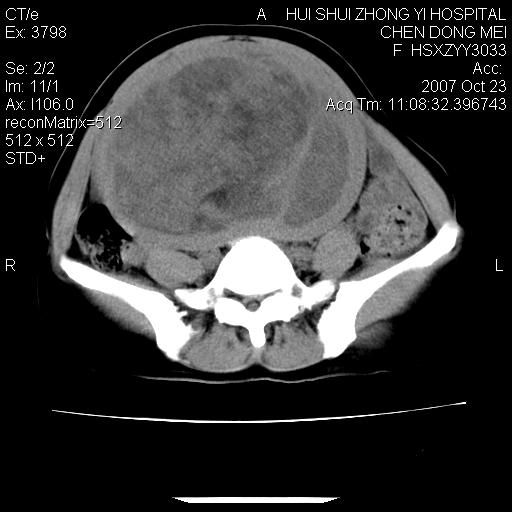

标题: CT10156:女.43岁,发现中下腹部包都块2年 [打印本页]

标题: CT10156:女.43岁,发现中下腹部包都块2年

发现中下腹部包都块2年。2年来月经不规律。

腹腔巨大软组织密度影,边缘光滑,包膜完整,内囊变坏死。腹膜后及盆腔内淋巴结肿大。结合病史考虑卵巢癌可能性大。

病变巨大,呈囊实性改变,包膜较厚且完整,内见分膈,周围脏器明显受压移位,病变与左侧附件关系密切,考虑来源左侧附件的囊腺瘤,不除外癌变可能;畸胎瘤可能性较小。

2年了,边缘还光整,未见明显周围侵犯,未见腹水等,病灶\"单发\"考虑\"超级\"子宫肌瘤,楼上各位所述不排除

病变巨大,呈囊实性改变,包膜较厚且完整,内见分膈,周围脏器明显受压移位,病变与左侧附件关系密切,考虑来源左侧附件的囊腺瘤,盆腔内见肿大淋巴结,不除外癌变可能。

病变巨大,呈囊实性改变,包膜较厚且完整,内见分膈,周围脏器明显受压移位,病变与左侧附件关系密切,考虑来源左侧附件的囊腺瘤,不除外癌变可能